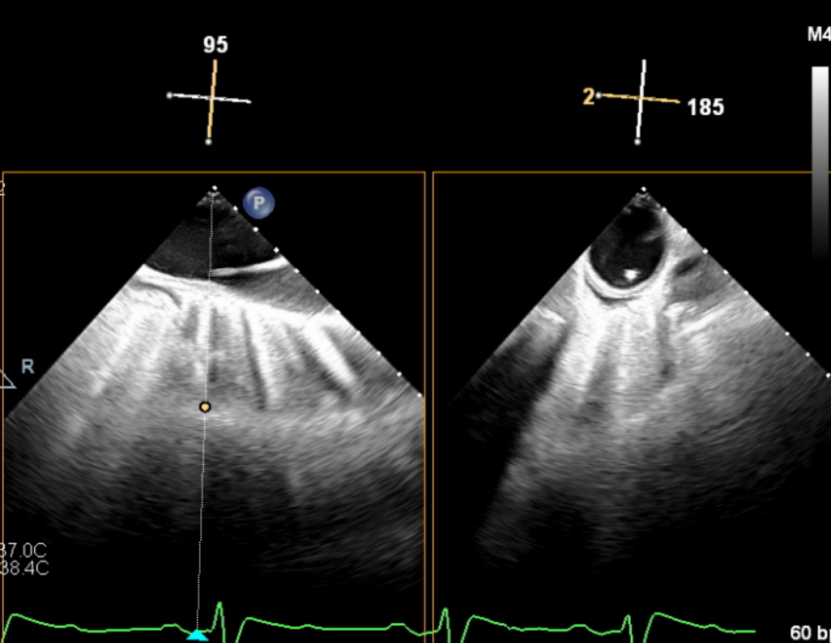

输送器顺利跨瓣,释放外鞘管,开始定位释放,超声评估可见定位件入窦可,后释放内鞘管,打开瓣架,瓣叶活动良好,无瓣周反流,综合考虑瓣膜稳定良好,脱钩释放。

(定位件入窦)

(瓣膜展开)